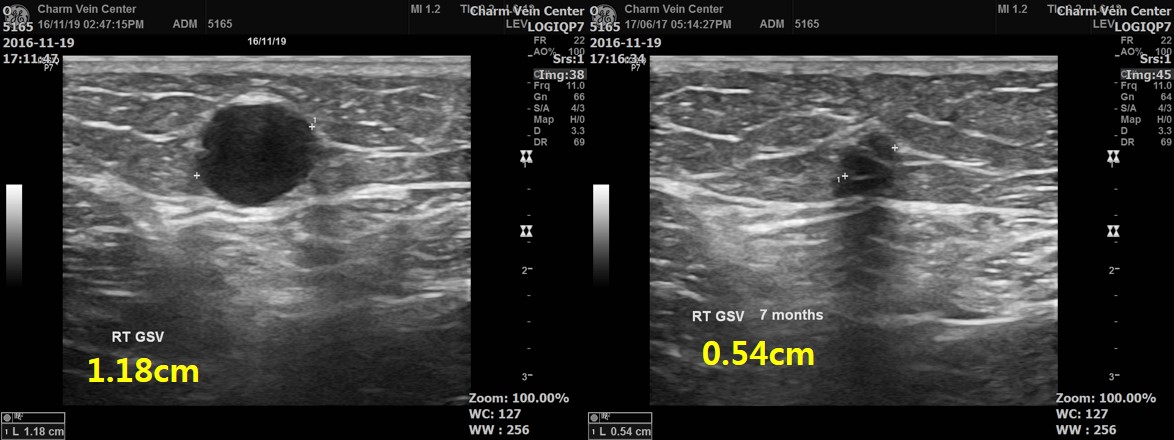

수술전과 7개월의 변화를 사진을 비교해봅니다

기존의 혈관이 폐쇄되어서 서서히 퇴화가 되는 것이 확인됩니다